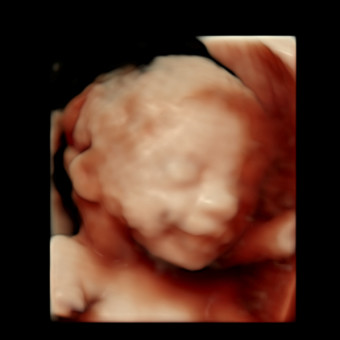

Baby Moberg

Ashley & Jeremy Moberg

June 1, 2026

We're thrilled that Riley is almost here! Your love and support mean everything to us, and we're so grateful you're joining us to celebrate. While gifts are always appreciated, your presence is the greatest joy we could ask for - thank you for being here to share in our excitement!